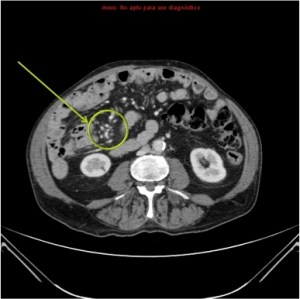

Se revisarón estudio previos, en un enema baritado y TC se observó:

Enema baritado con ciego (con apéndice visible) en posición anómala, localizado en hipocondrio izquierdo. TAC de adomen con signo de remolino o Twister de vasos. Otro hallazgo sería encontrar la VMS a la izquierda de la AMS.